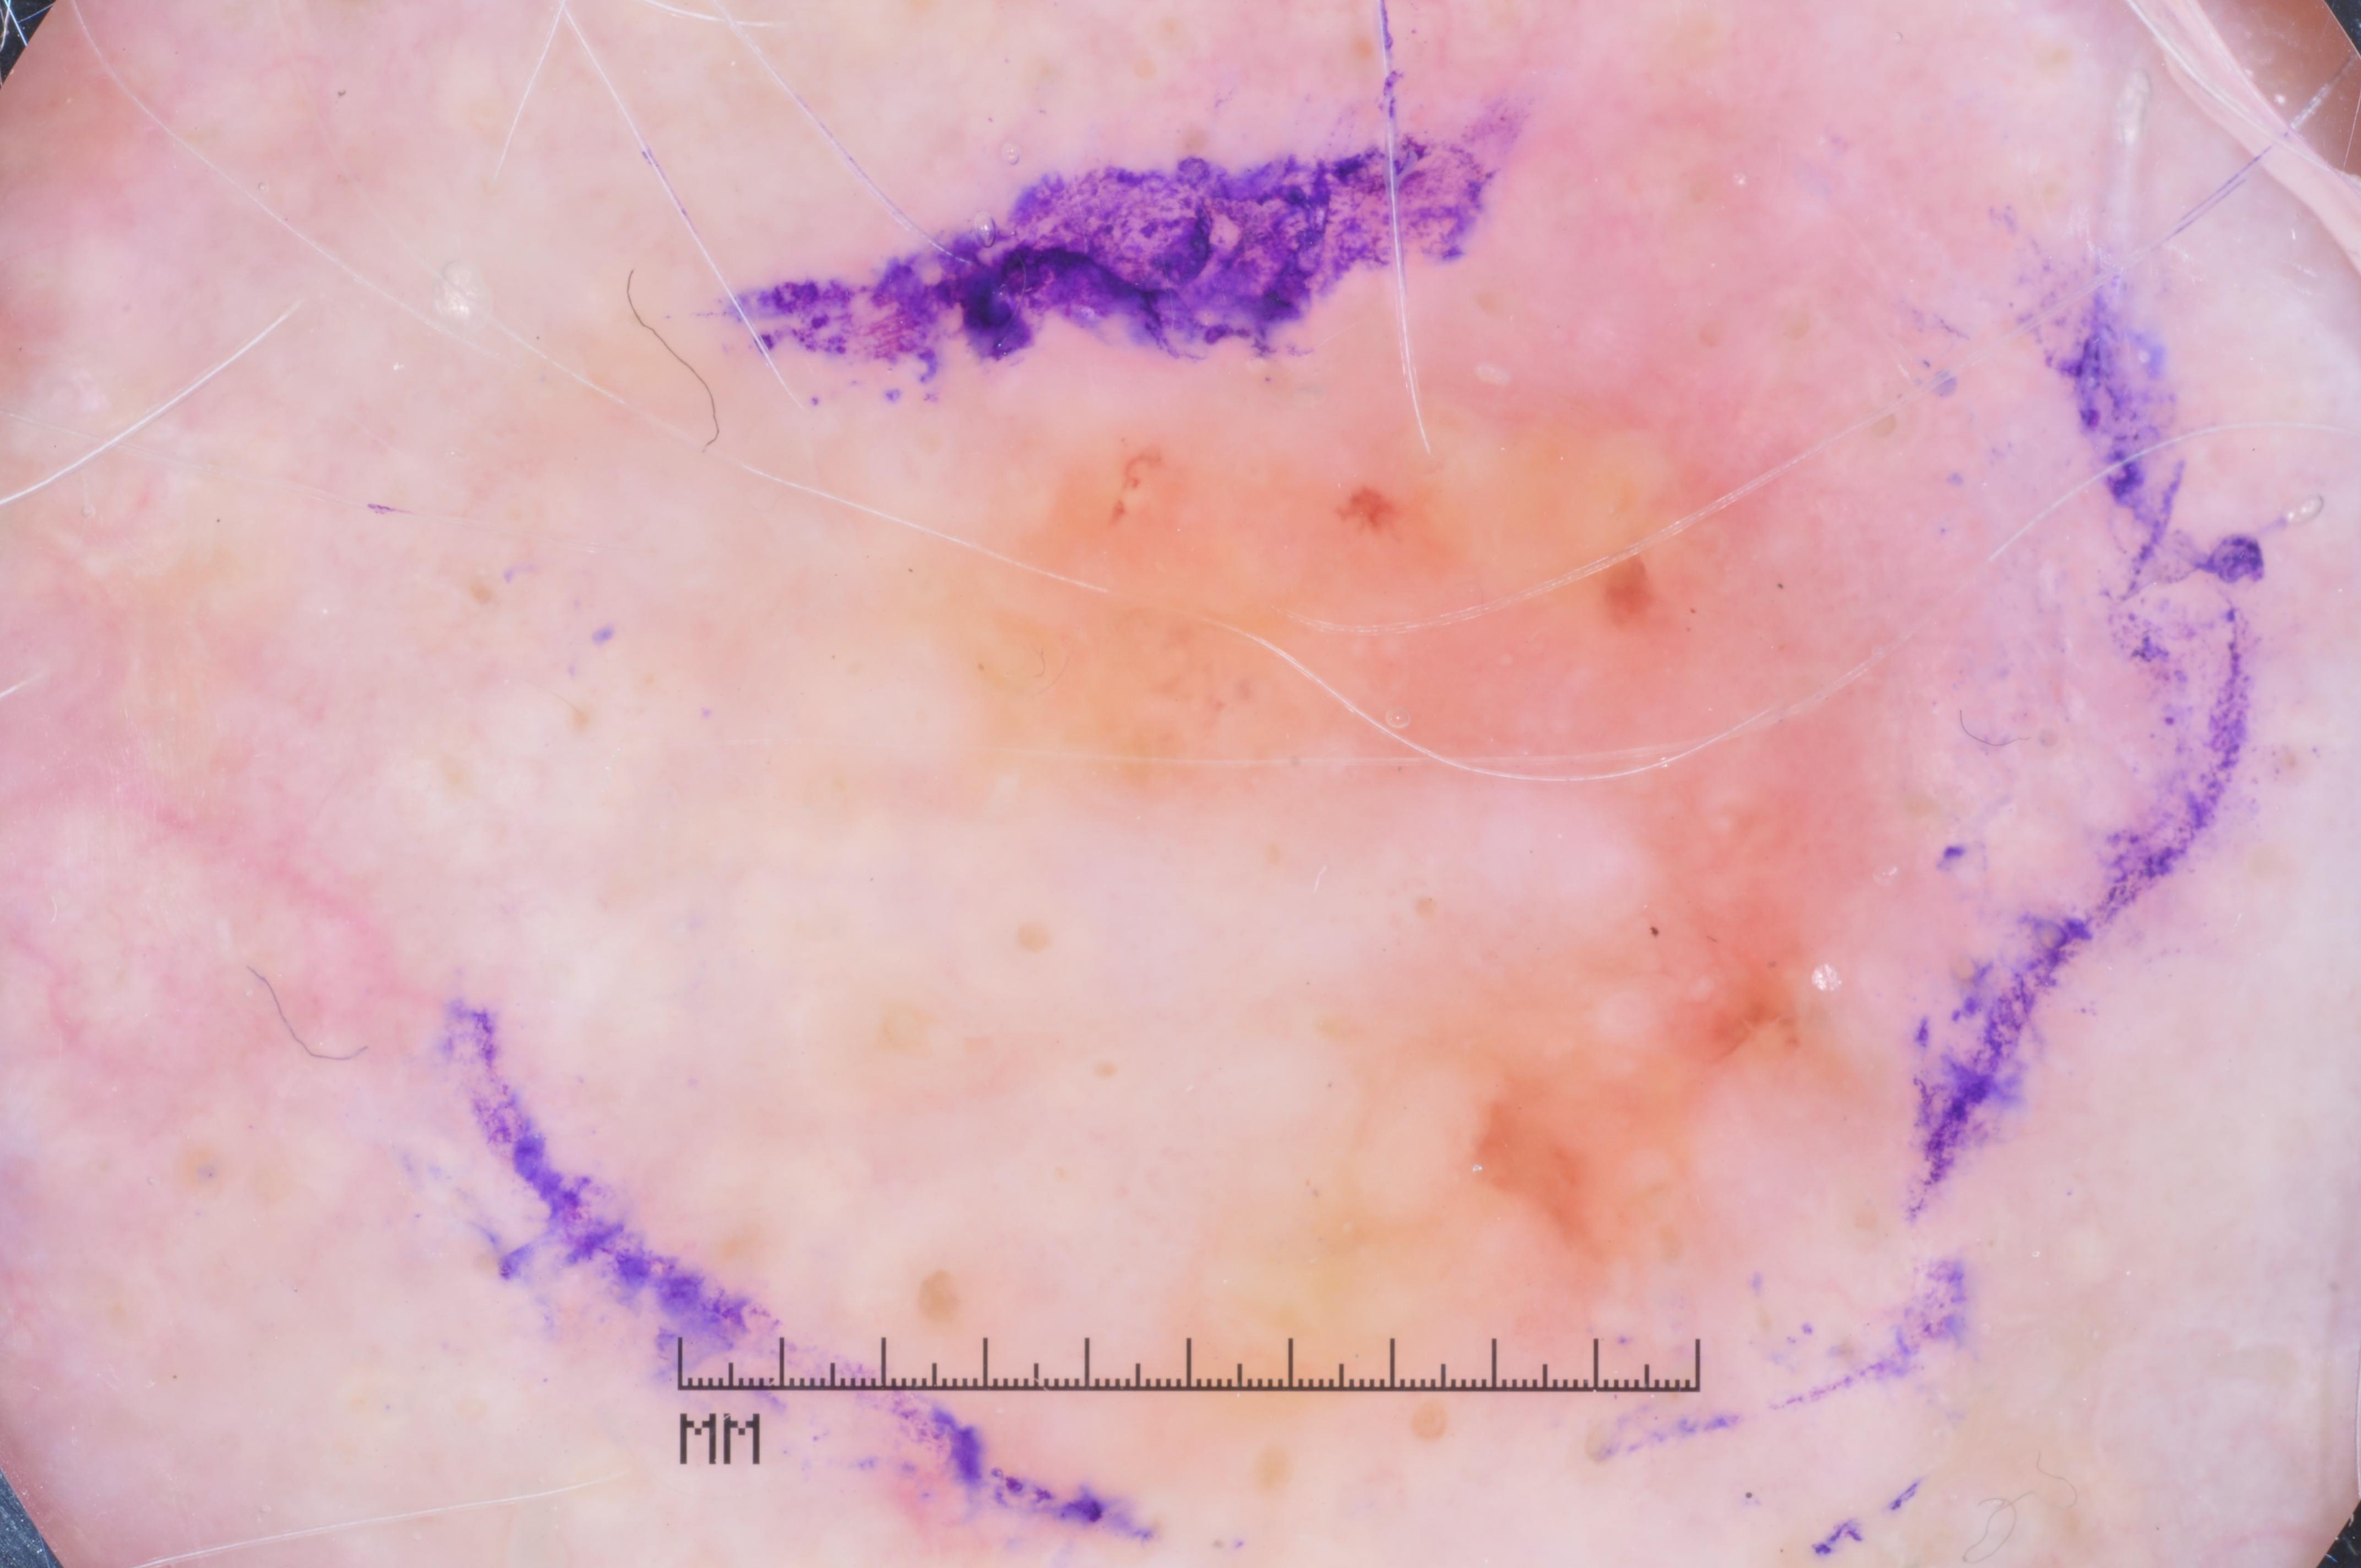

{

"age_approx": 75,

"anatom_site_general": "head/neck",

"concomitant_biopsy": true,

"dermoscopic_type": "contact non-polarized",

"diagnosis_1": "Malignant",

"diagnosis_2": "Malignant melanocytic proliferations (Melanoma)",

"diagnosis_3": "Melanoma in situ",

"diagnosis_confirm_type": "histopathology",

"image_type": "dermoscopic",

"lesion_id": "IL_7473586",

"melanocytic": true,

"sex": "female"

}